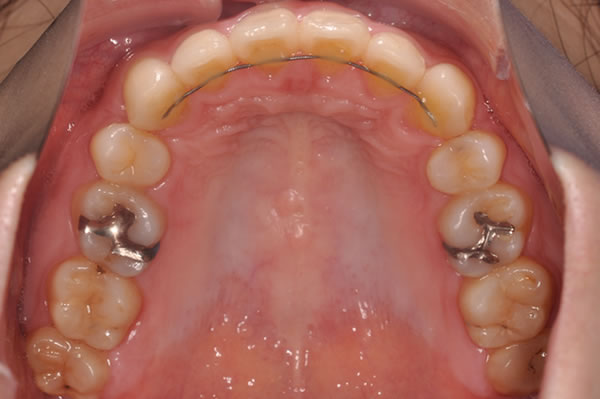

装置 |

||

![]() |